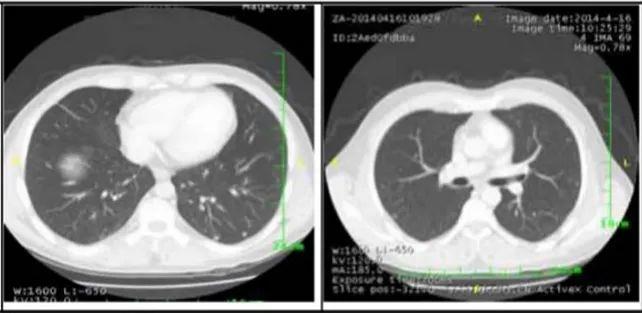

2. 肺部病灶治疗前后核磁对比:

肺部转移病灶在用药后2个月明显缩小,4个月后病灶基本消失。

治疗2个月

治疗4个月

治疗6个月

治疗16个月